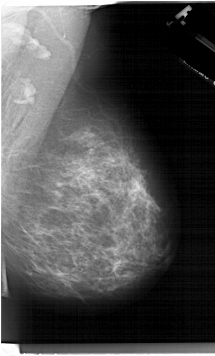

A_1284_1.LEFT_MLO

LEFT_MLO LINES 6616 PIXELS_PER_LINE 4096 BITS_PER_PIXEL 12 RESOLUTION 43.5 OVERLAY

RIGHT_CC LINES 6571 PIXELS_PER_LINE 3916 BITS_PER_PIXEL 12 RESOLUTION 43.5 NON_OVERLAY